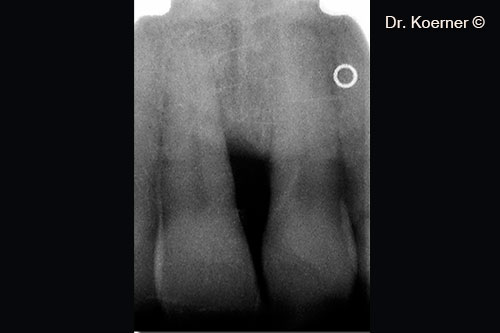

X-ray situation 4 months post-op with splinting

X-ray situation 10 years post-op